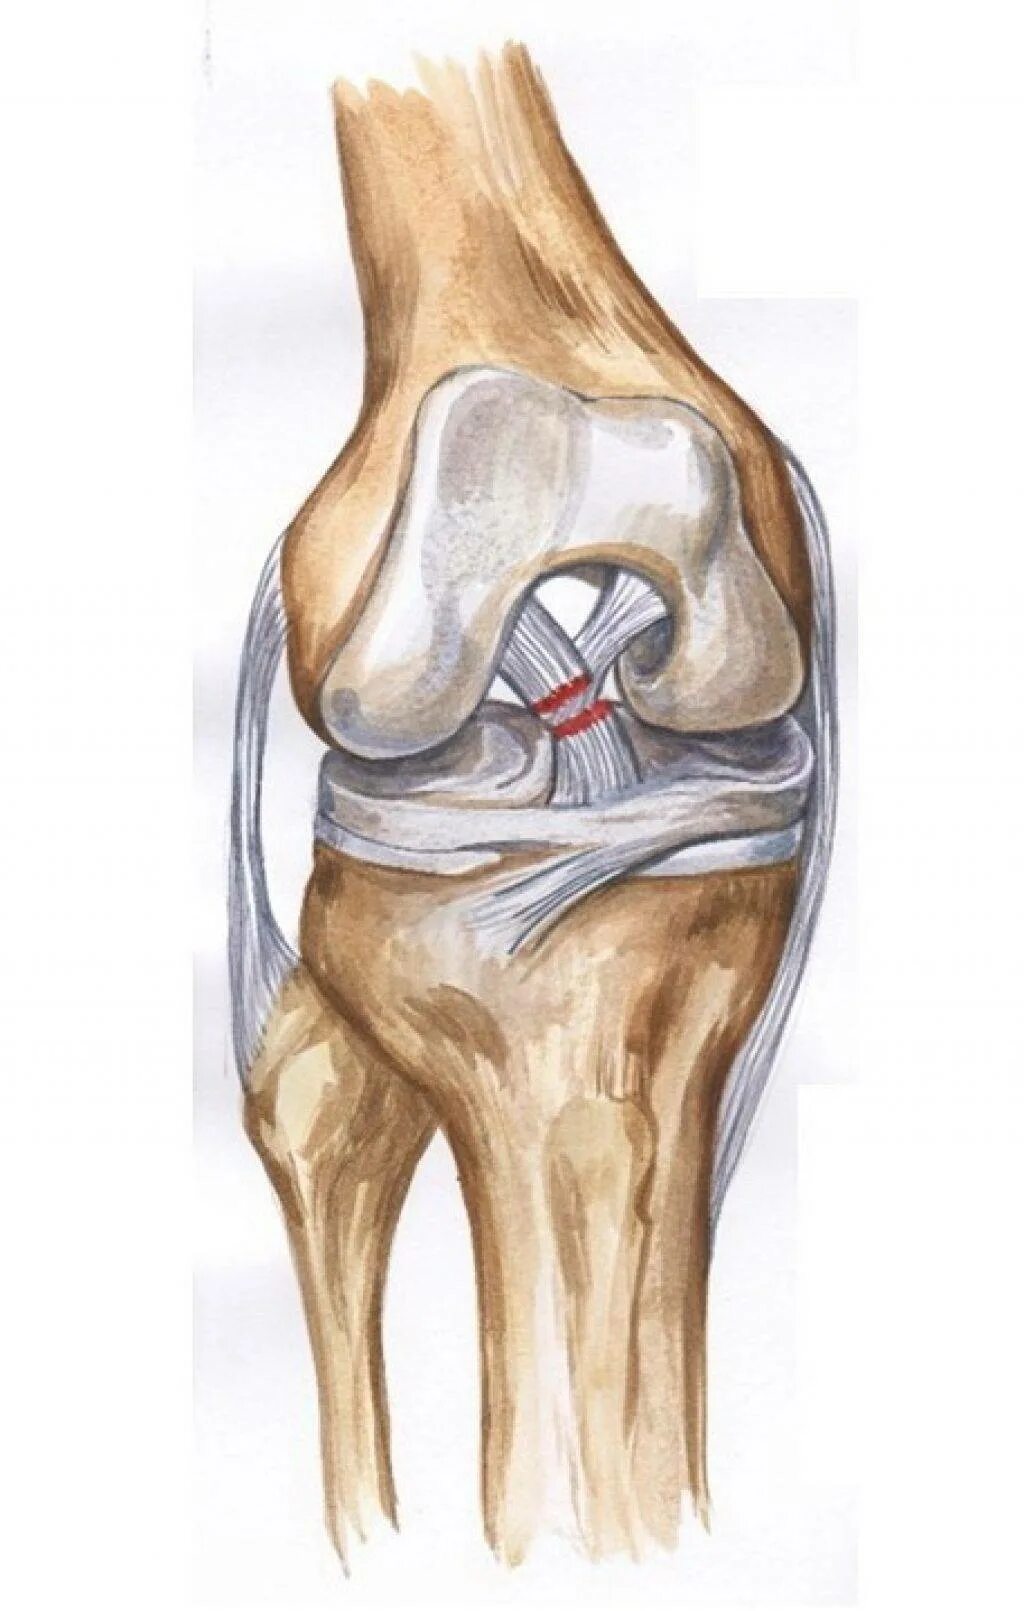

Разрыв коленного сустава 3 степени